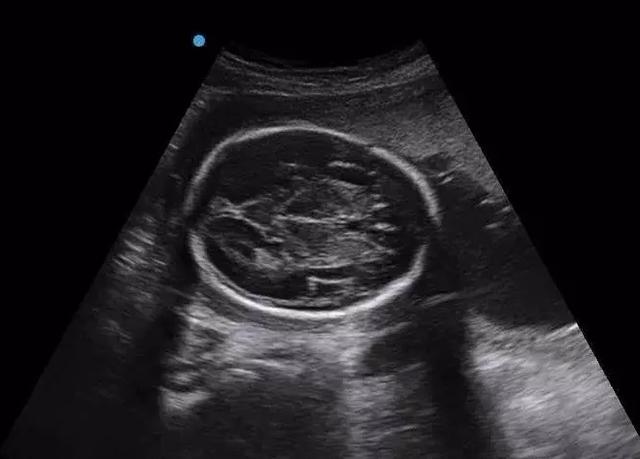

刚刚聊完腿短这个事情,妈妈又开始担心起宝宝的头大小问题,做个怀孕妈妈真是难啊。首先检查过程中没有宝宝不是脑积水,只是单纯的径线与孕周大,这不是什么大问题。为什么?继续往下看。